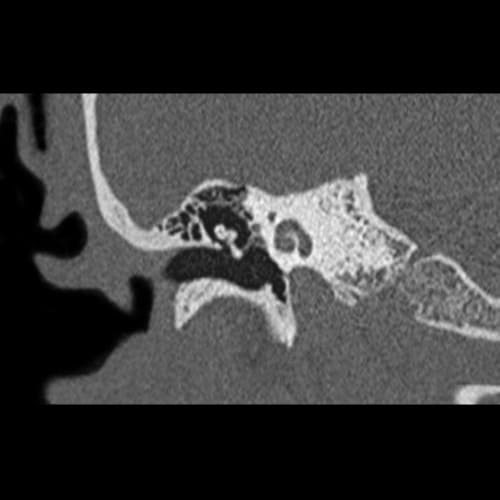

Axial